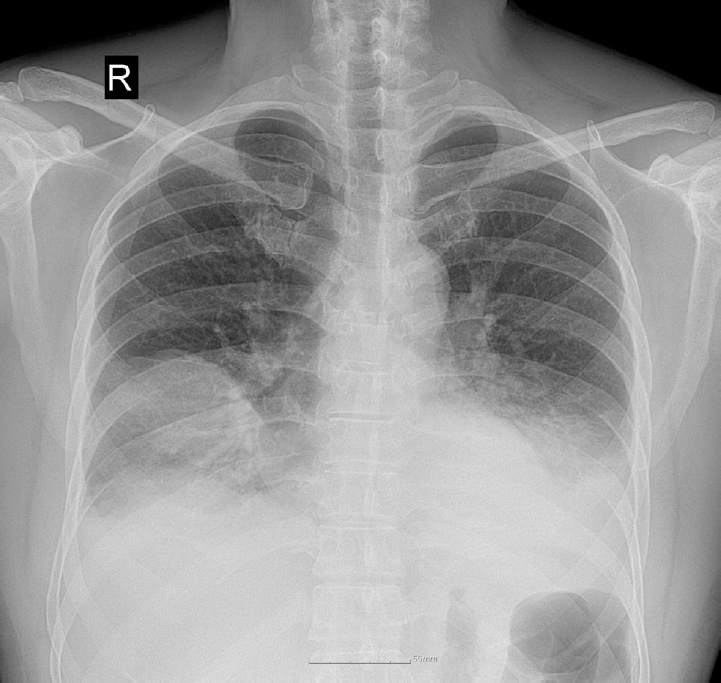

After surgery, the antibiotic regimen was modified. Piperacillin/tazobactam was discontinued after 8 days of treatment and the regimen was switched to cefepime, which was maintained for 21 days. Levofloxacin was administered intravenously for 15 days, followed by oral maintenance for 14 days. The patient’s condition improved steadily. He was transferred to the general ward on hospital day 11, and the chest tubes were removed on hospital day 15. By hospital day 28, follow-up chest radiography showed significant resolution of haziness in the right middle and left lower lobes (Fig. 4). Laboratory markers normalized, with WBC count of 8,200 cells/µL and CRP level of 0.37 mg/dL. The temporal changes in these inflammation-related biomarkers throughout the hospital stay are illustrated in Fig. 5. The comprehensive clinical course, encompassing the temporal relationship between symptom onset, diagnostic imaging, and therapeutic interventions, is summarized in Fig. 6. The patient was discharged on day 29 of hospitalization without further respiratory complications.

Fig. 4.

Near-complete resolution of multiloculated abscesses involving right middle and left lower lobes at follow-up computed tomography.

Fig. 4. Near-complete resolution of multiloculated abscesses involving right middle and left lower lobes at follow-up computed tomography.